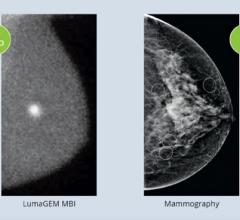

A study conducted by Mayo Clinic and published in the AJR has clinically confirmed that Molecular Breast Imaging (MBI) yields superior imaging and low radiation exposure for women with dense breast tissue, which can affect up to 40 percent of the female population.

Gamma Medica announced the company now offers Philips MicroDose SI, the first full-field digital mammography (FFDM) system that supports single-shot, non-invasive spectral imaging, as a complement to its market leading LumaGEM Molecular Breast Imaging (MBI) system. LumaGEM is a highly effective and cost-efficient technology for detecting breast cancer in patients with complex mammograms and dense breast tissue. The agreement with Philips will enable Gamma Medica to provide breast imaging suites with the option to purchase both technologies and offer the most advanced and safest commercially available dense breast solution for women. Philips will continue selling MicroDoseSI directly to customers.